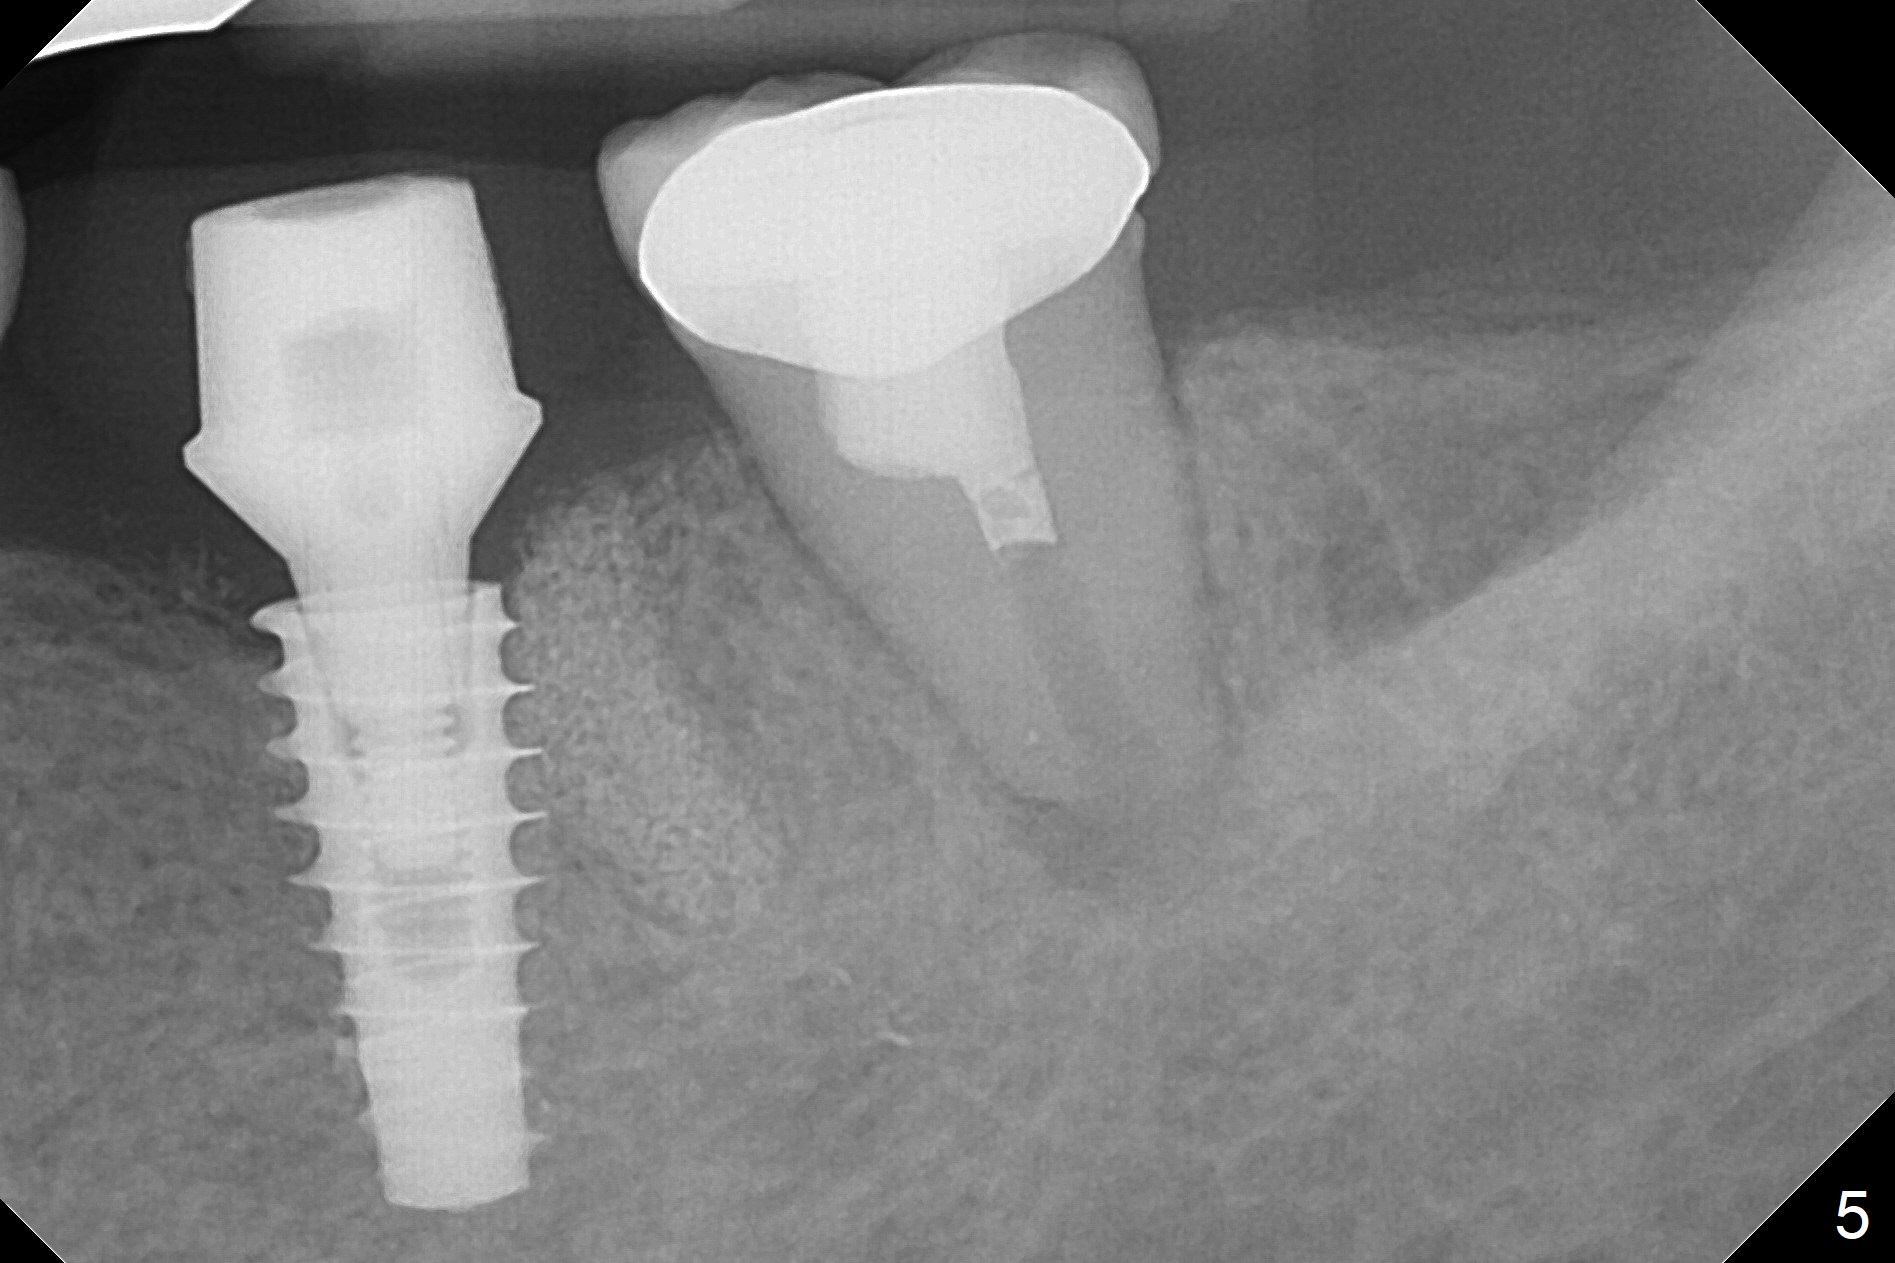

After making a 10 mm incision at the site of #19, #15c blade is used as an osteotome to start bone expansion, followed by Magic Split and Magic Expander (ME, 3 mm in diameter).  The depth is approximately the bottom of the mesial socket.  The osteotomy beyond the socket has to be done with 1.6 mm pilot drill (Fig.1) in combination of ME.  Following ME 4.3 mm and Magic Drill (MD) 3.8 mm for 15 mm (gingival level), a 4.5x11 mm dummy implant is placed with 50 Ncm (Fig.3); the implant looks narrow for the edentulous space.  After ME 4.8, MD 4.3 for 13 mm and Final Drill for 15 mm, a 5x11 mm IBS is inserted with >50 Ncm (Fig.3).  With 2 more turns of the implant, a 6.5x4(2) mm abutment is placed (Fig.4).  Periodontal dressing is applied around the abutment for additional retention.  A provisional is fabricated 3 weeks postop.  The provisional and abutment are loose 4 months postop (Fig.5).  After retightening the abutment, impression is taken for final restoration.  There is no bone loss 1 year 3 months post cementation (Fig.6).  After use of #100 file (Fig.7), the canal is debrided with #140 file with 1.5 mm shorter in working length with placement of Calcium Hydroxide paste.  Pain gets worse post RCT retreatment. There is limited native bone for primary stability when an immediate implant is placed (red dashed line: the superior border of the Inferior Alveolar Canal).  Prepare IS regular and extra wide kits and tissue-level implants (>5 mm).  Socket preservation may be done instead.  If the socket is large and the vein is not so small, prepare PRF.  In fact blood drawing fails.  When the tooth is extracted, it is sensitive to remove granulation tissue.  Socket preservation is done with Vanilla graft at #18 (Fig.8); there is ~3.5 mm bone between the bottom of the single socket and the Inferior Alveolar Canal (red dashed line).  The socket at #18 seems to have healed 4 months post extraction (Fig.19), but the bone height appears to have been reduced (compare Fig.10,11).  The buccolingual width is also decreased (Fig.12,13).  A 4.5 or 5.0x10 mm implant is appropriate for the site (Fig.14).  There is no bone loss at #19 (which may be associated with the bone expansion) 1.5 years post cementation (Fig.15).  Therefore the osteotomy at #18 will be assisted with bone expanders after 2.2 mm drill.